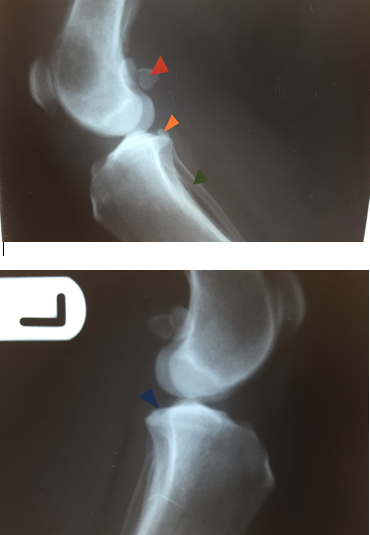

On this radiograph (2/22) identify the labelled structures (red, blue, orange, green).

Red = sesamoid bones in gastrocnemeus m. (fabellae)

Blue = intercondylar eminence

Orange = popliteal sesamoid bone

Green = fibula